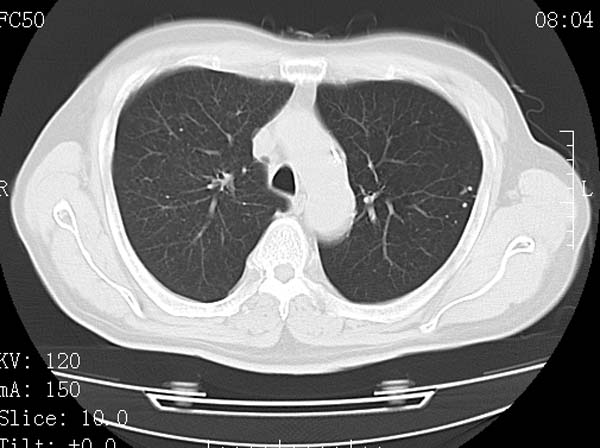

以下是引用守望可可西里在2008-6-24 1:11:00的发言:[br][br] 考虑为周围型肺癌:[br] 1.分叶结节,形态极不规则,蟹足样伸展的恶性浸润特征比较明确。[br] 2.磨玻璃影中由多个更高密度小结节聚集呈梅花瓣样。[br] 3.局部胸膜凹陷征比较明确。[br][br] 另:纵隔胸膜明显增厚、粘连。

以下是引用zjzjr在2008-6-24 11:19:00的发言:[br]支持左下肺周围型肺癌伴右肺转移,纵隔淋巴结转移,心包积液.

以下是引用zhangling在2008-6-24 14:56:00的发言:[br]我们科室意见报告为[br][br]1考虑左下肺周围型肺癌[br]2右肺小结节考虑转移瘤,纵隔淋巴结转移[br]3心包积液. [br] 各位老师分析的相当好 谢意[br]